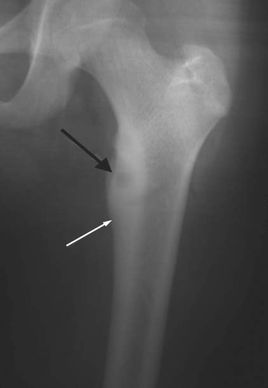

骨樣骨瘤是一種成骨性良性腫瘤,多見于兒童和青少年,好發(fā)于下肢長骨。其臨床特征是患部疼痛,阿司匹林可止痛。病理特征是有一個(gè)小而圓的骨組織核心,由骨樣組織和不成熟骨小梁組成,周圍為硬化骨。X線顯示骨干增粗致密,其中有一約1cm直徑X線透亮區(qū),中央有一小致密影,周圍為硬化帶。將腫瘤核心的“巢穴”及周圍硬化骨予以切除即可治愈。